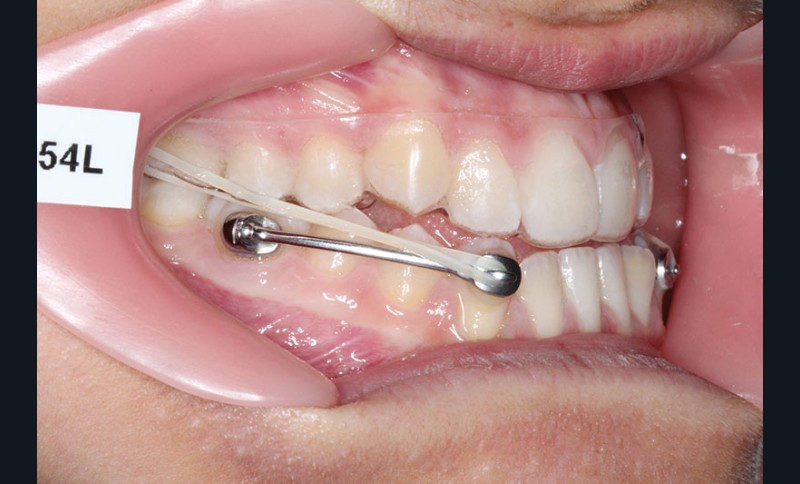

1re phase : recul des secteurs latéraux mandibulaires avec le Motion Classe III Carriere (fig. 4 à 6)

Nous mettons en place des bras latéraux Motion associés à des élastiques intermaxillaires ancrés sur des brackets sur 17 et 27 et une gouttière thermoformée maxillaire portée jour et nuit :

• 1er mois : élastiques 6 oz. 1/4”

• 2e mois et suivants : élastiques 6 oz.1/4“

L’objectif de cette étape est d’obtenir un recul des secteurs latéraux mandibulaires afin de positionner les molaires et canines en classe I et de réorienter le plan d’occlusion en haut en avant.